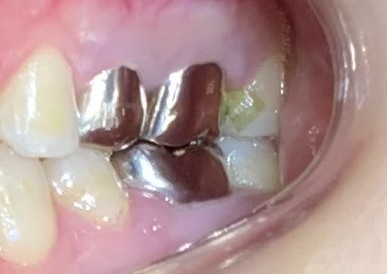

●金属の被せ物で、歯の頭の部分は補強できても根の部分は補強できない

神経の治療をした歯は、残った部分を補強するために金属セラミックなどの丈夫な素材の被せ物をします。しかし被せ物で補強できるのは歯ぐきの上の歯の頭部分だけで、その下の歯の根の部分は補強できません。

●金属の土台が入っているとクサビの力がかかる

神経の治療をした歯でも、特に金属の土台が入っている歯は歯が割れるリスクが高くなります。金属の土台は歯よりも固く、噛む力が加わるたびに歯に対してくさびのような力がかかります。それが繰り返されることにより、金属の土台との境目から歯が割れやすくなります。